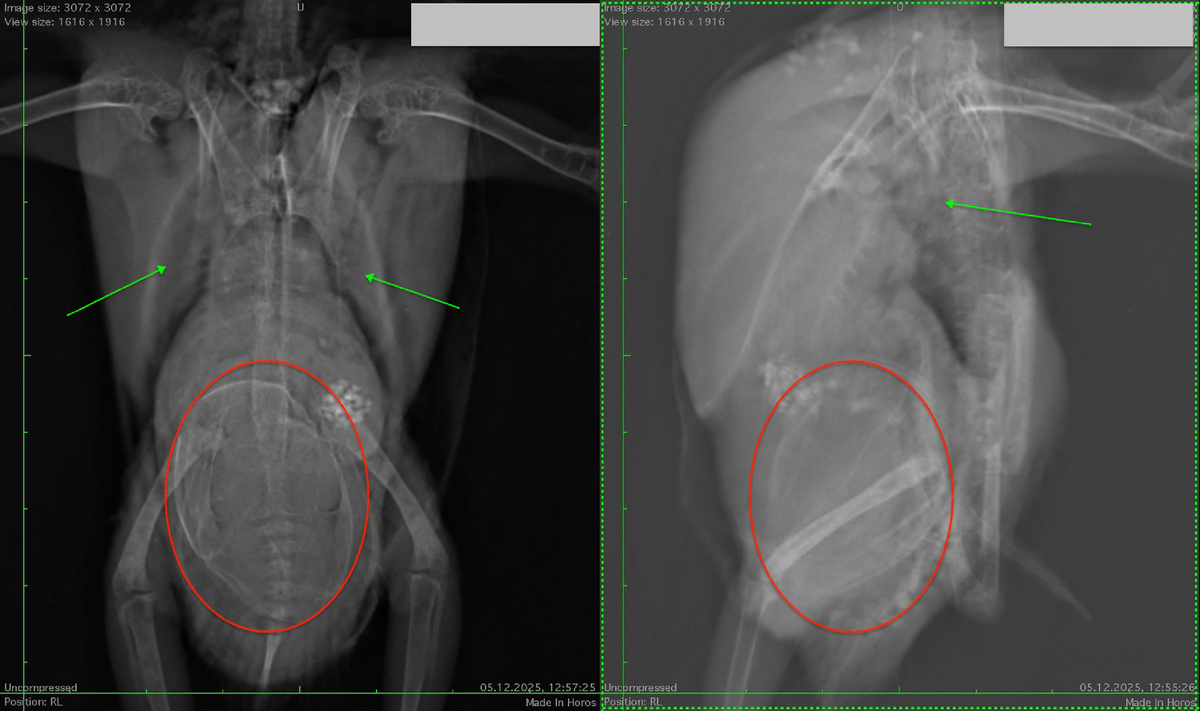

Случай из моей практики. Корелла 7 лет. Периодически неслась. Но потом стала грустной, нахохленной и малоподвижной. Сделали рентген. В клинике где нет птичьих врачей решили, что у птицы киста. А у кореллы дистоция - то есть, затруднённая яйцекадка, попугай уже давно не мог снестись. Яйца обведены красным.

рентген попугая с дистоцией. Птица не может снести яйца уже очень давно

Кроме этого, основная причина затруднённой яйцекладки отмечена зелёными стрелками - сливная пневмония. На снимке, конечно же, много и других патологий, но всё это следствие хронической системной инфекции.